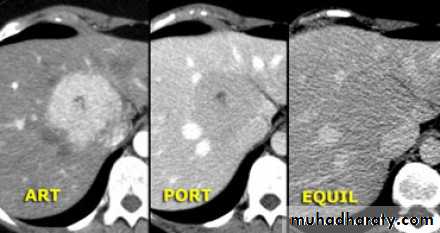

Malignant neoplasms:

hepatocellular carcinoma

Hemangioma